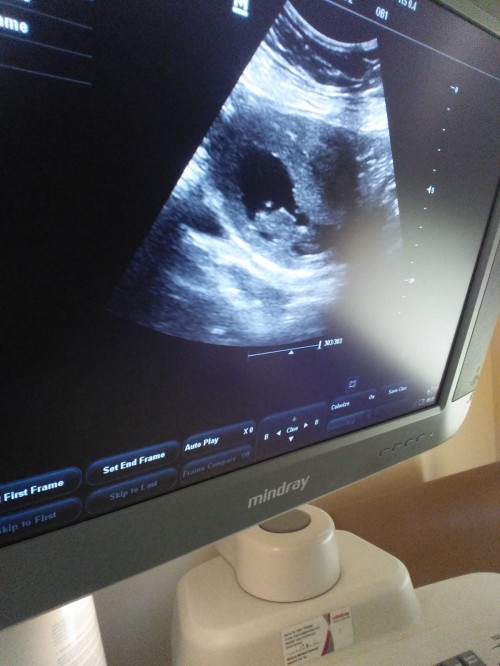

Maşallah sana canım şuan anlattığın kadarıyla gerçekten  iyi anladım peki bir de ablaminki  var onada bakarmisin atsam

Bakarim canim

Attın canım fotyu

imagebu kuzum iste

kac haftalik bu canim nub icin 11 12 13 haftalik olmasi gerek bu daha sekil almamis buyuk yanilma payiyla beraber kiz diyesim geldi ama nub a gore demiyorum nubu gorunmuyor cunku kizlar gec sekil alir ondan kiz diyorum

Vu 12 haftalık kuzum